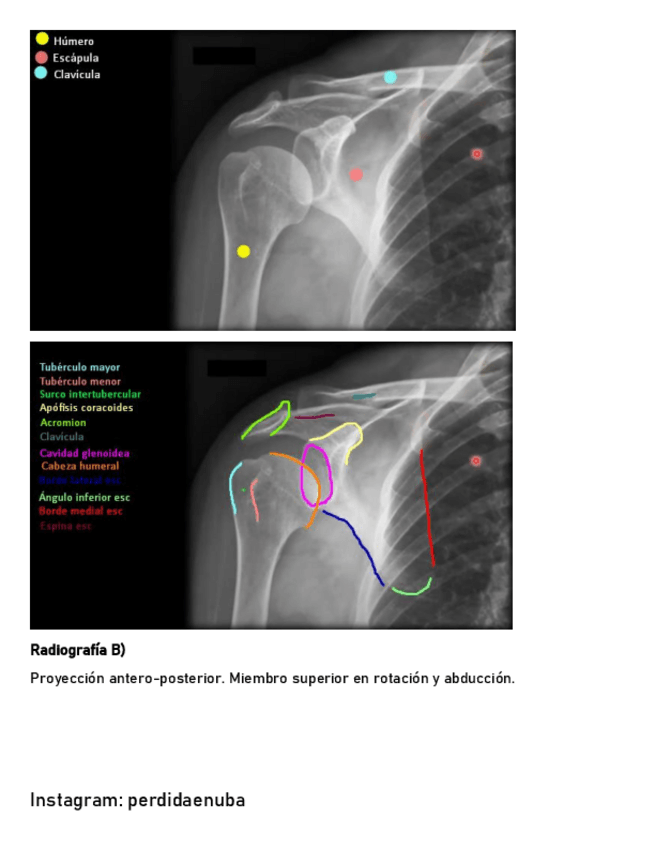

He publicado nuevos apuntes de 8º Cirugía General: CINTURA-PECTORAL-1.pdf

17 páginas